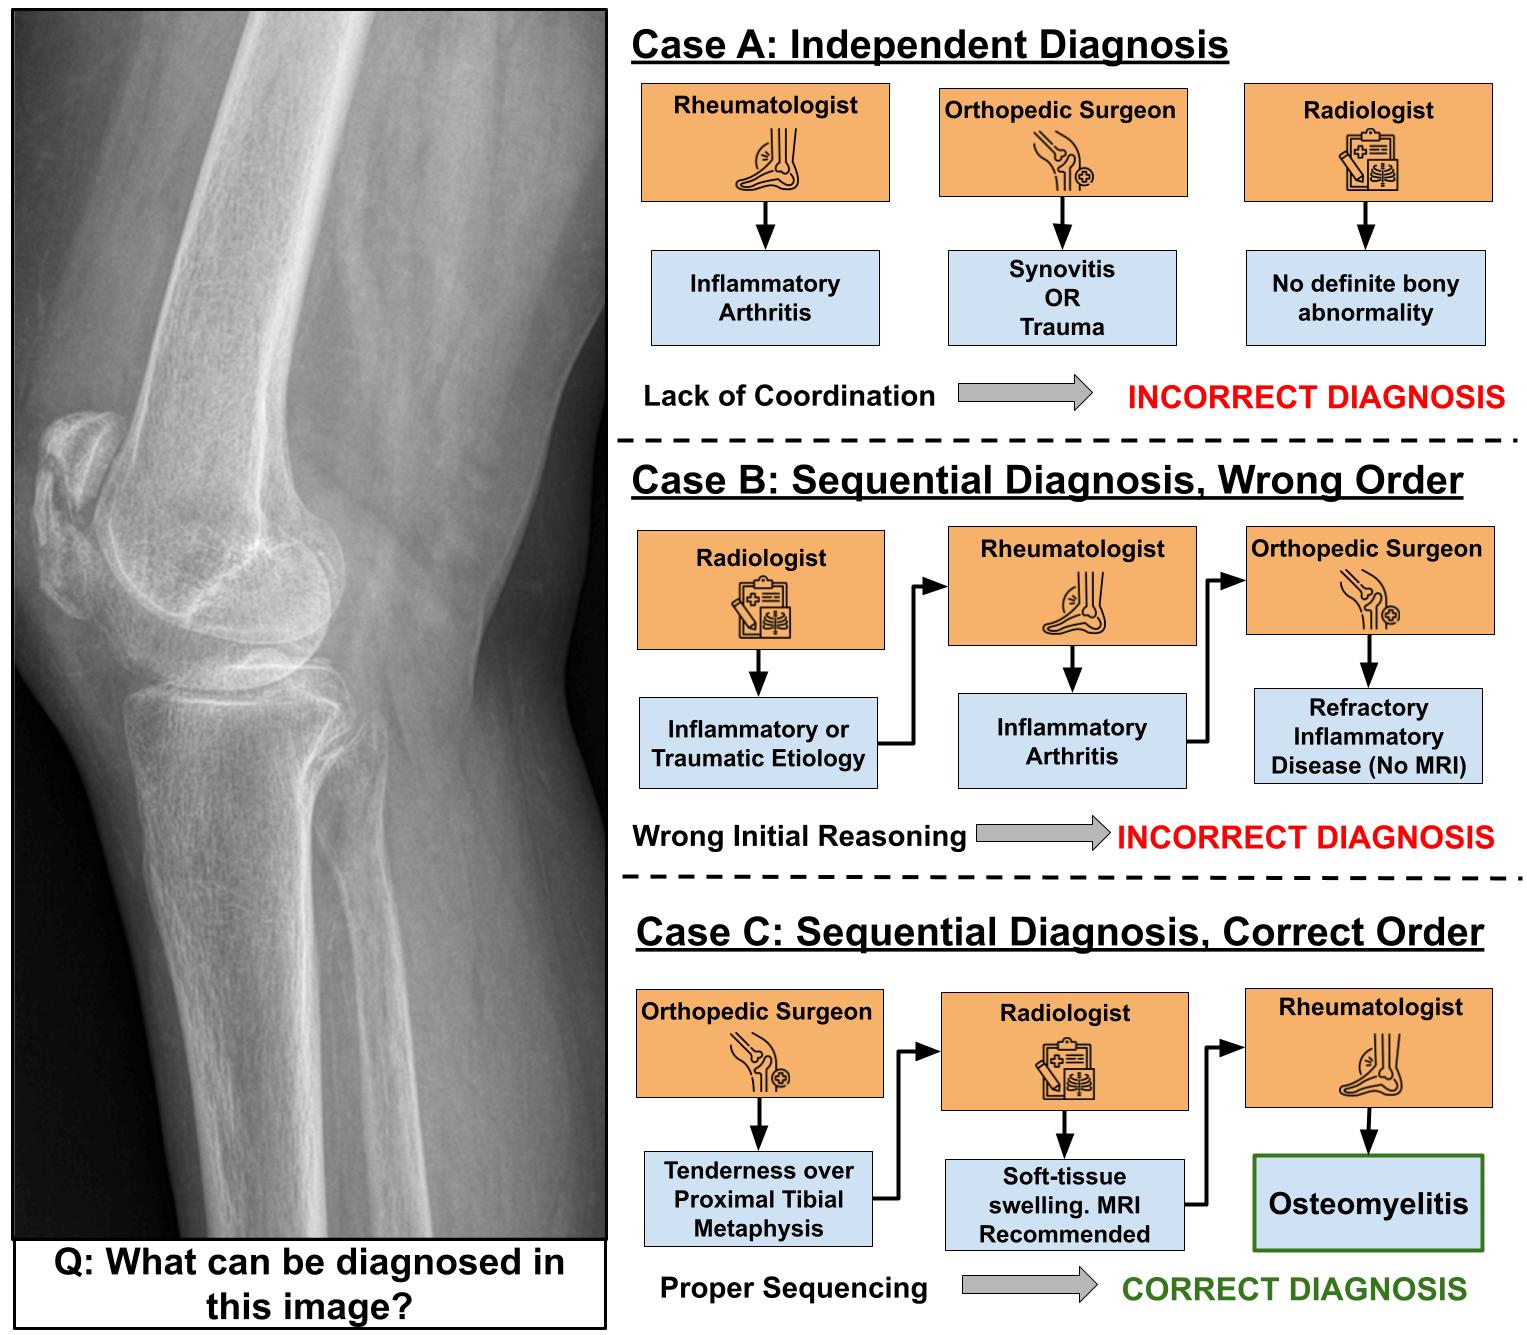

Qualitative Example